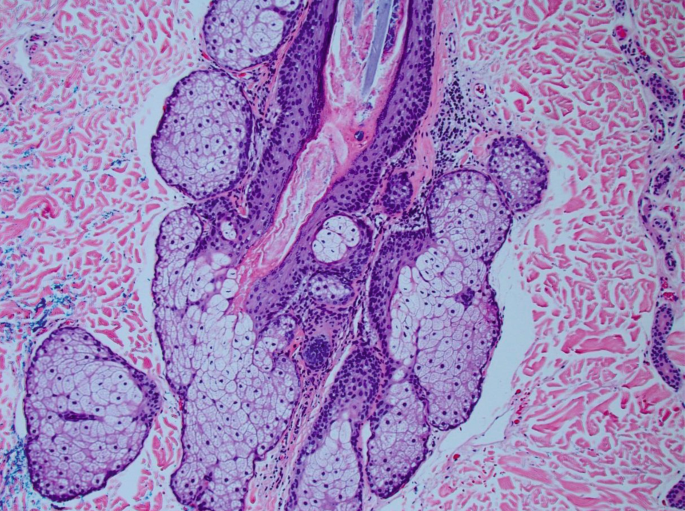

The composition of the epidermis dermis and subcutaneous fat is reviewed in great detail. This chapter discusses the structure histology and function of the skin. Practice all cards Apocrine glands Coiled structures attached to hair follicles found in.

Tiny grains of pigment Coloring matter that are produced by melanocytes and deposited into cells in the stratum germinativum layer of the epidermis and in the papillary. Skin and skin appendages are influenced by sex hormones. Physiology and Histology of the Skin Exam Review Milady Standard Workbook Cengage 2020 ISBN 978 - 1 - 3370 - 9504 - 4 Chapter 3 - Physiology and Histology of the.